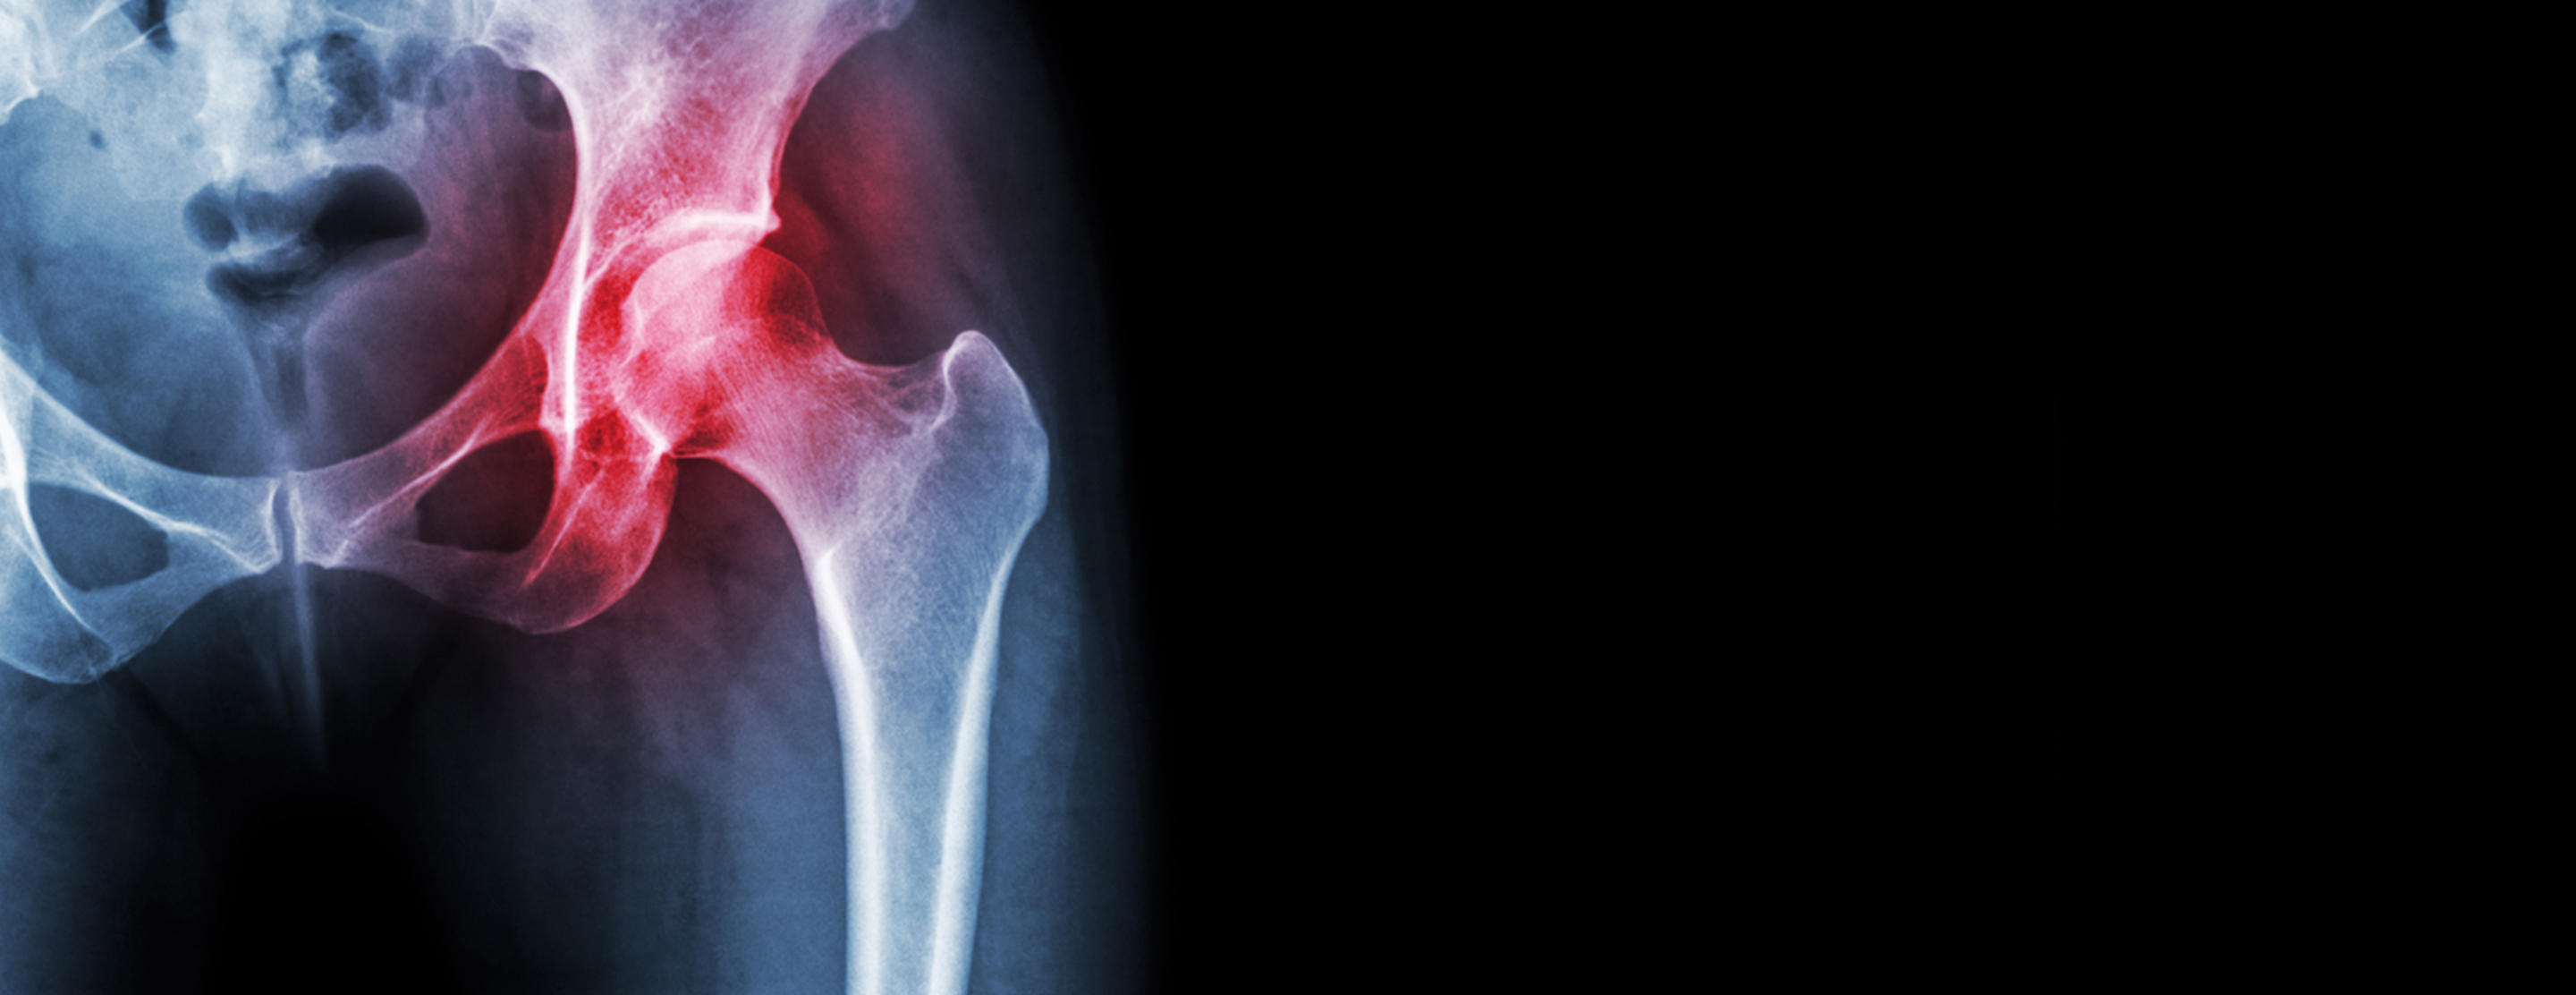

Injury to the joints can cause pain in the legs, lower back, groin, buttocks, knees, shoulders and hips. Pain may occur from injury, simple wear and tear or an inflammatory disease, such as rheumatoid arthritis.

A joint is where the ends of two bones meet. They allow movement from side to side, up and down, and in rotation. A special lining covering the ends of bones, called cartilage, stops the bones from rubbing together and allows easy, smooth movement. If cartilage becomes worn down, the bones rub together during movement, causing significant pain.

- Hip joint injection